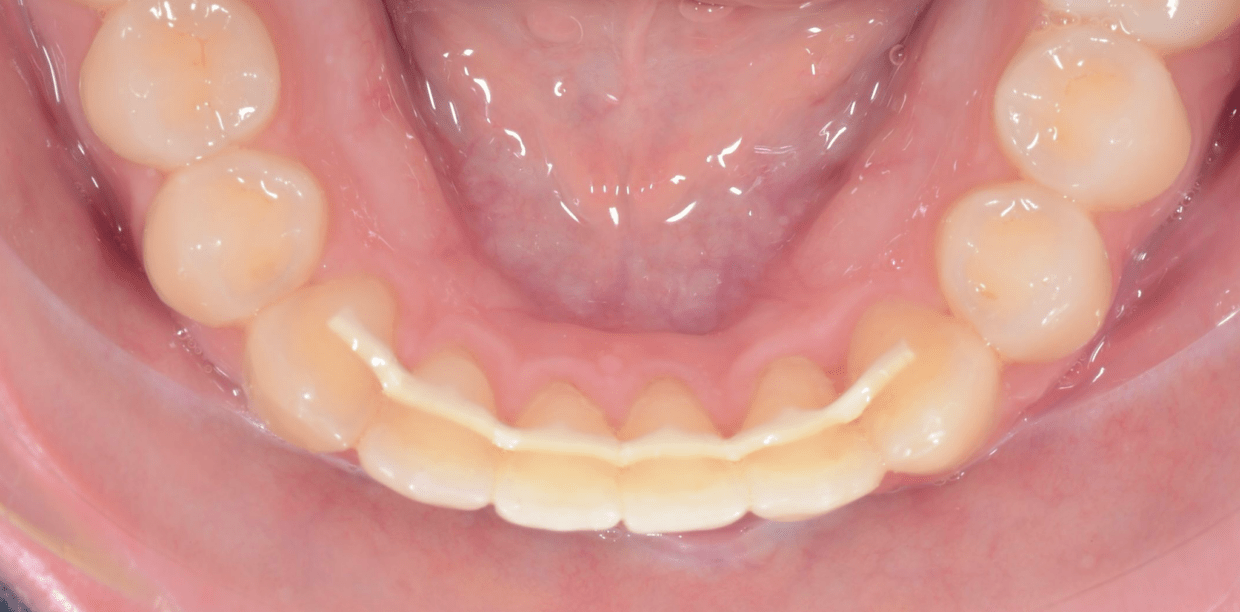

Cas cliniques

Simple - White

Simple - White

Simple - White

Simple - White

Simple - White

Simple - White

Simple - White

Simple - White

Simple - White

Simple - White

Simple - White

Simple - White

Simple - White

Simple - White

Simple - White

Simple - White